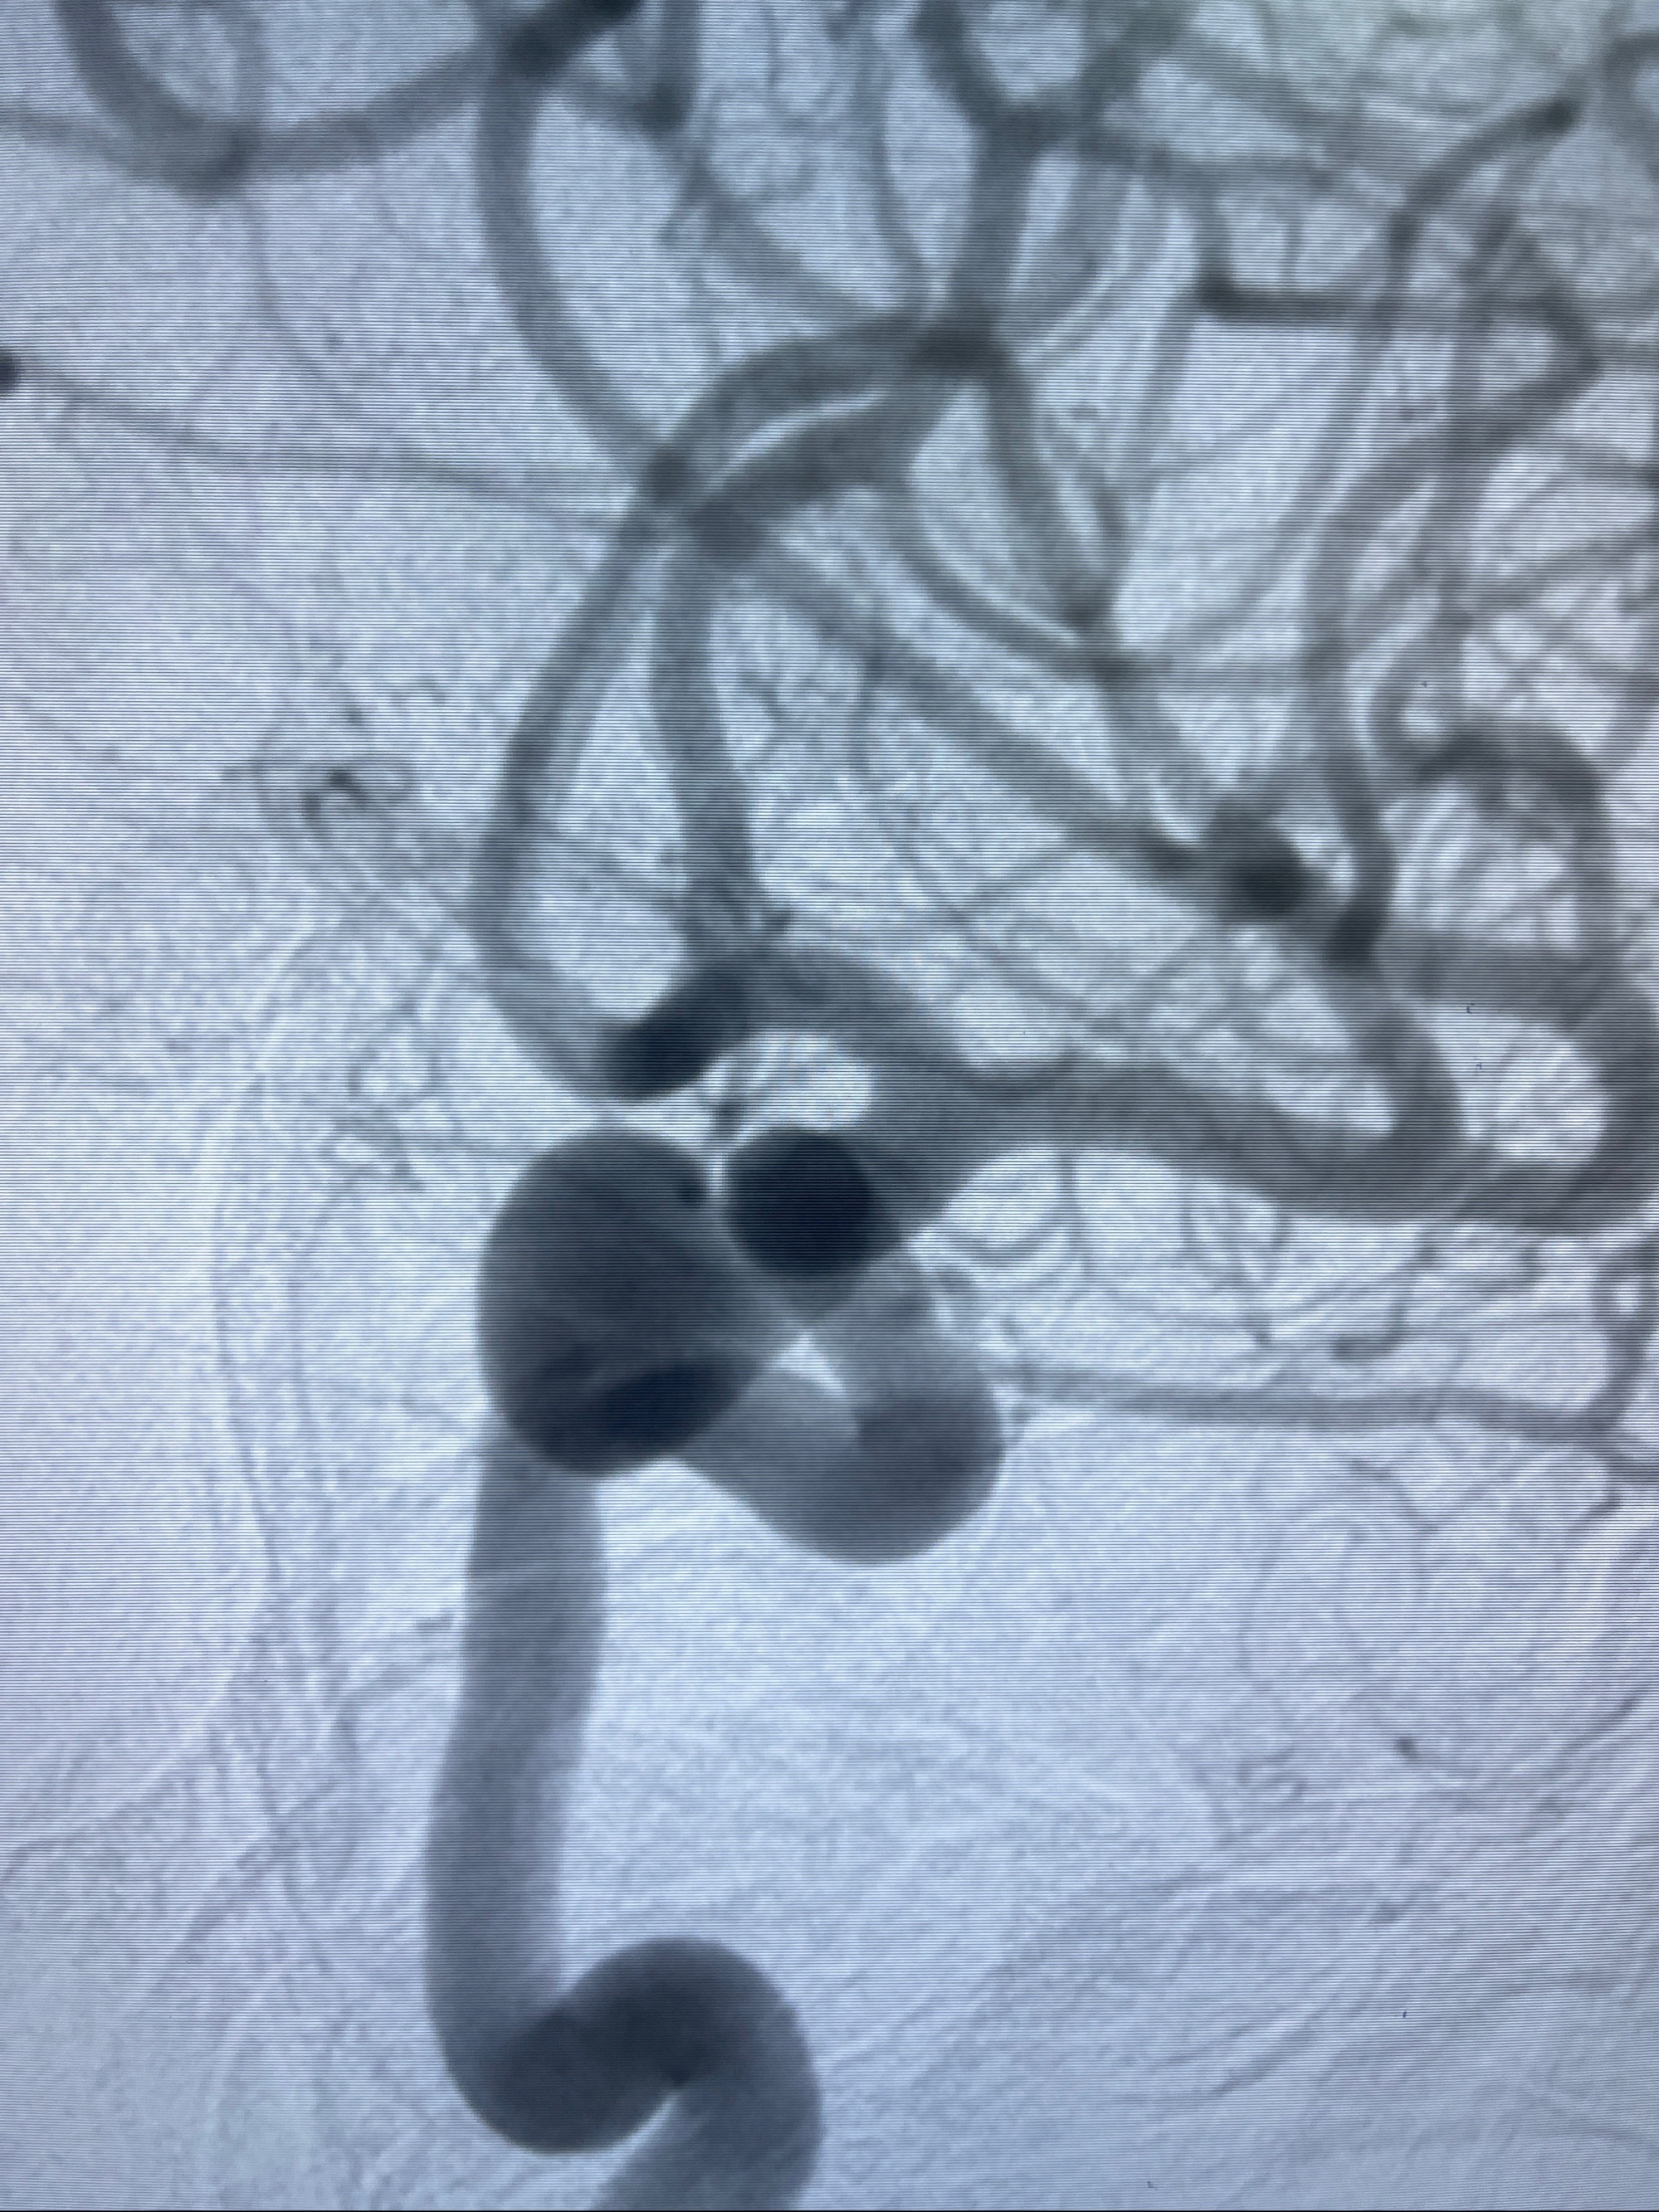

2023-08-30DSA:左侧颈内动脉眼动脉动脉瘤,约3*9.2*7.3mm大小